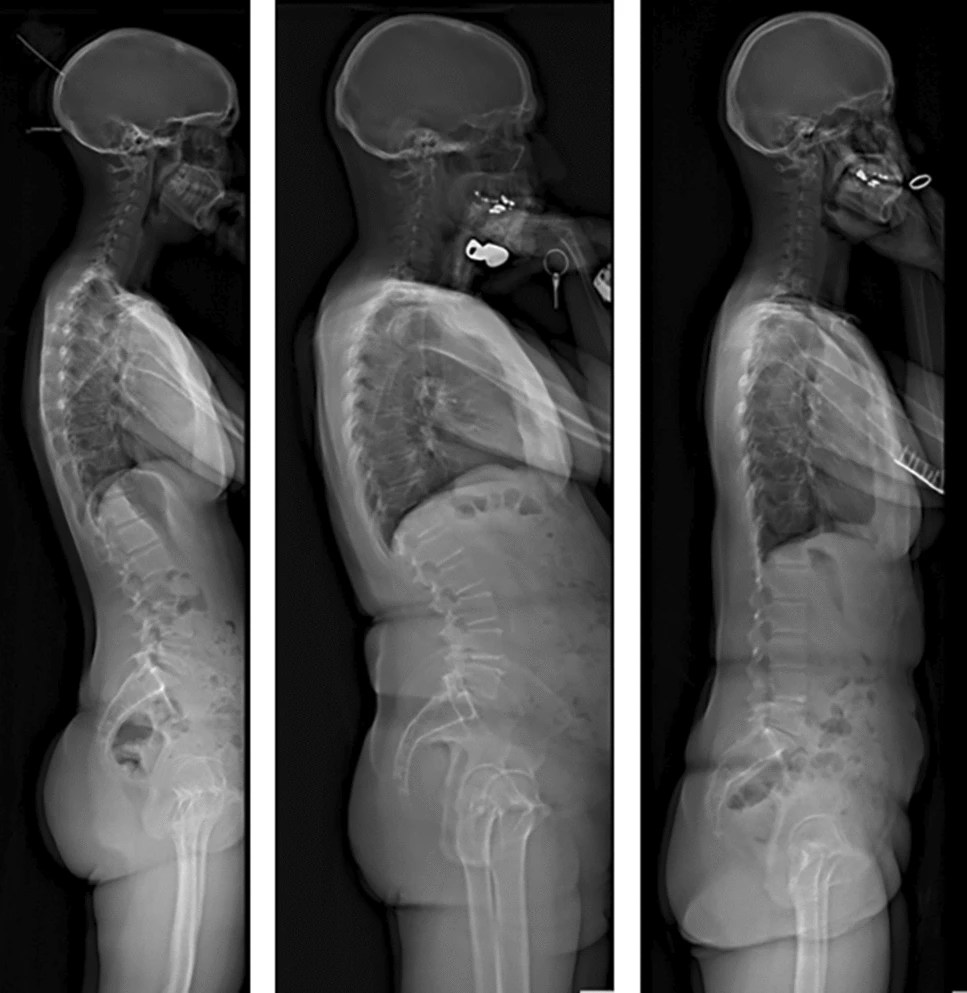

We found that asymptomatic volunteers used compensatory mechanisms such as slight pelvis retroversion, knee flexion, and neck extension to maintain an aligned sagittal posture with their head centered over their knees (Not the pelvis).

In asymptomatic volunteers, sagittal alignment parameters saw a slow and steady change across age groups most exemplified by an increase in Thoracic kyphosis, while lumbar lordosis did not show a significant decrease across age groups.